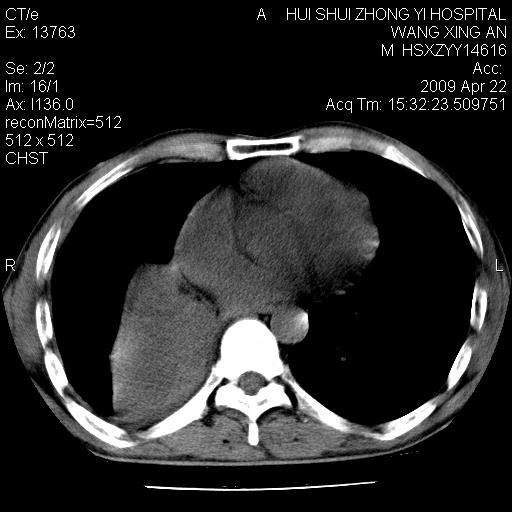

标题: CT19534:患者男、46岁咳嗽、胸痛半月。 [打印本页]

标题: CT19534:患者男、46岁咳嗽、胸痛半月。

考虑---右肺中心型肺癌继发下叶不张,少量胸水。

支持右侧中央型肺ca并右下肺不张、右侧胸腔少量积液。

右侧中心性肺癌并下叶肺不张,双肺及纵隔淋巴结转移,右侧胸腔积液

1、右下肺中央型肺癌并右肺转移,右肺下叶不张。(肿块围绕右肺下叶支气管生长,致管腔闭塞右肺下叶不张;右肺有结节影)。

2、右侧胸腔积液。

3、右中上肺陈旧性肺结核(右肺见纤维化病灶及点状钙化)。

1、右下肺中央型肺癌并右肺转移,右肺中下叶不张。(右肺有结节影)。胸骨转移

1)右肺中间段支气管癌并右肺下叶肺不张。2)右肺上叶、两肺下叶背段感染性病变。3)右侧少量胸腔积液。